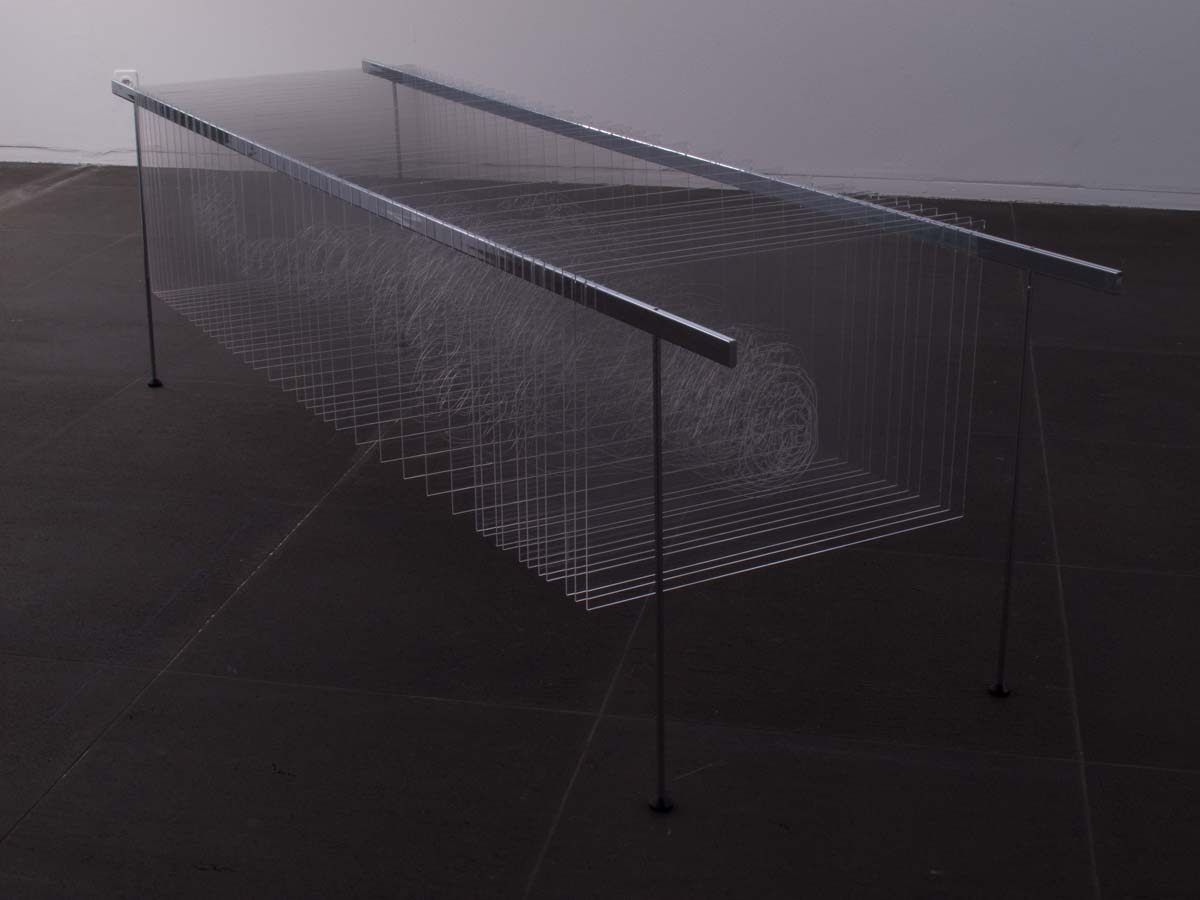

Découpe et gravure laser sur plexiglas, acier chromé 94 x 82 x 228 cm

41 coupes ont été sélectionnées et dessinées pour reformer le corps de Joseph Paul Jernigan, exécuté par injection au Texas en 1993. Ayant légué son corps à la science, il a été sectionné en 1878 tranches de 1 mm puis entièrement numérisé, ce qui a permis la création en 1994 du Visible Human Project, premier corps humain virtuel.